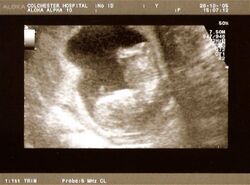

A dating scan at 12 weeks

Obstetric ultrasonography is routinely used for dating the gestational age of a pregnancy from the size of the fetus, determine the number of fetuses and placentae, evaluate for an ectopic pregnancy and first trimester bleeding, the most accurate dating being in first trimester before the growth of the foetus has been significantly influenced by other factors.[22] Ultrasound is also used for detecting congenital anomalies (or other foetal anomalies) and determining the biophysical profiles (BPP), which are generally easier to detect in the second trimester when the foetal structures are larger and more developed.[23]

X-rays and computerized tomography (CT) are not used, especially in the first trimester, due to the ionizing radiation, which has teratogenic effects on the foetus.[24] No effects of magnetic resonance imaging (MRI) on the foetus have been demonstrated,[25] but this technique is too expensive for routine observation. Instead, obstetric ultrasonography is the imaging method of choice in the first trimester and throughout the pregnancy, because it emits no radiation, is portable, and allows for realtime imaging.[26]

The safety of frequent ultrasound scanning has not been confirmed. Despite this, increasing numbers of women are choosing to have additional scans for no medical purpose, such as gender scans, 3D and 4D scans.[27] A normal gestation would reveal a gestational sac, yolk sac, and fetal pole.[28]

The gestational age can be assessed by evaluating the mean gestational sac diameter (MGD) before week 6, and the crown-rump length after week 6. Multiple gestation is evaluated by the number of placentae and amniotic sacs present.[29]